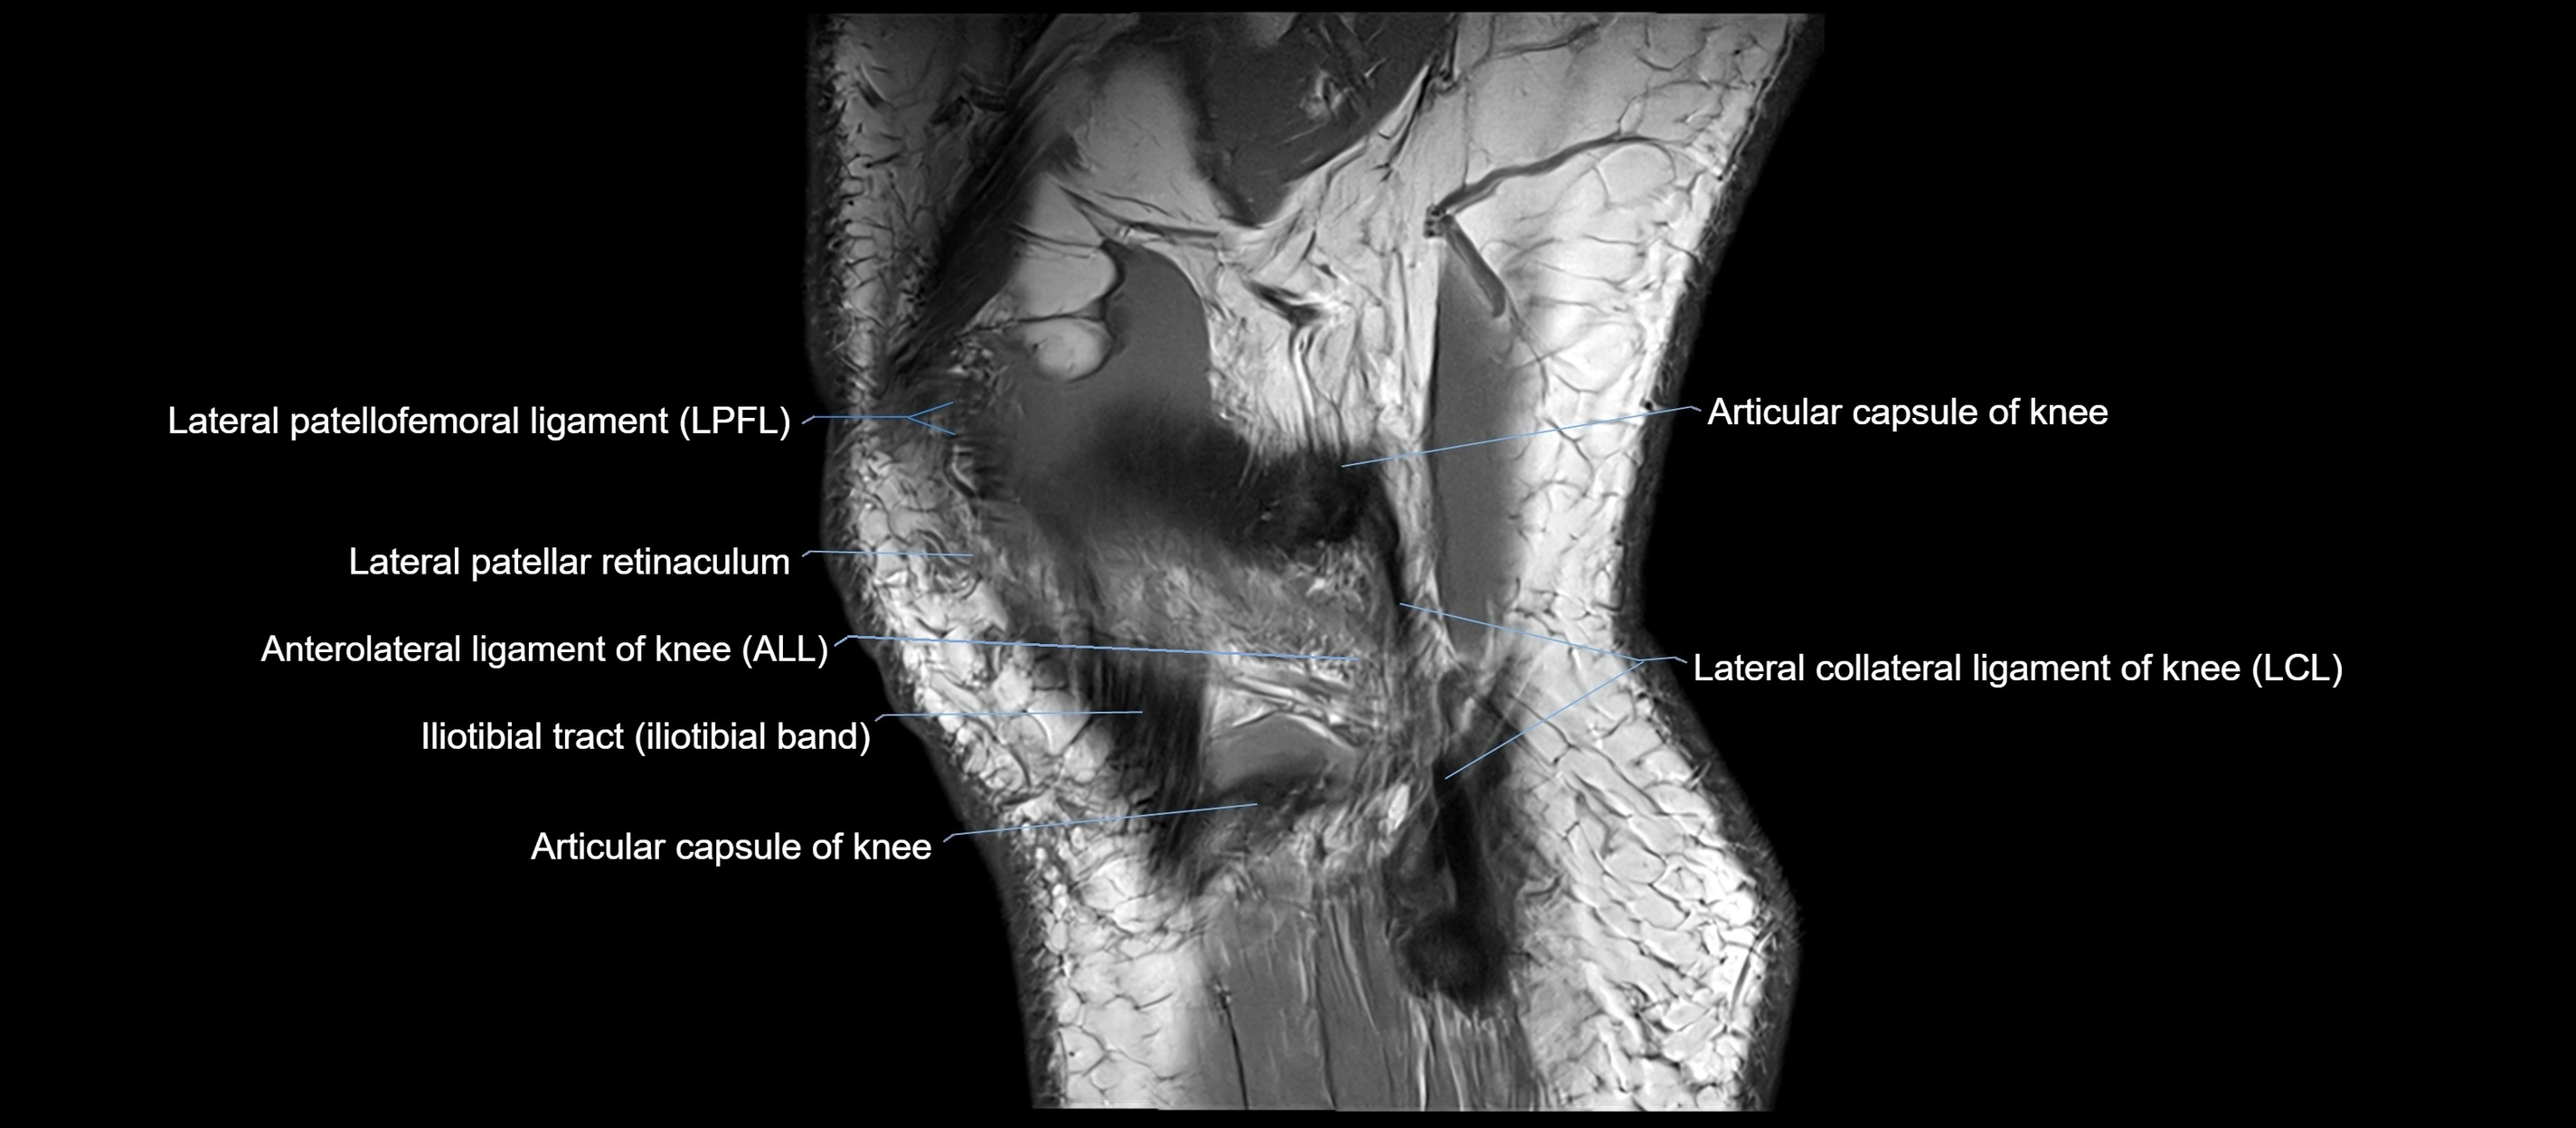

MRI images

image